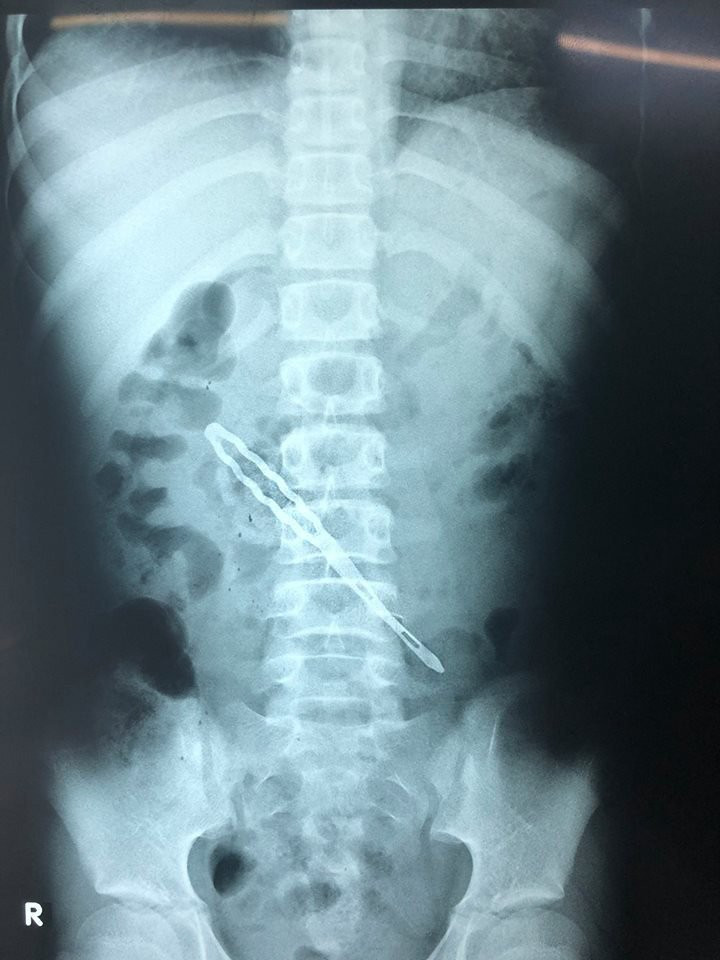

Chiếc kẹp tóc có 2 cách đâm thủng thành sau tá tràng.

Sau phẫu thuật, các bác sĩ lấy ra dị vật là chiếc kẹp tóc có 2 nhánh, mỗi nhánh dài 5cm đâm thủng thành sau tá tràng xuyên mạc treo ruột non vào ổ bụng gây viêm phúc mạc. Do phần tá tràng nằm phía sau phúc mạc nên việc lấy dị vật tương đối khó khăn.